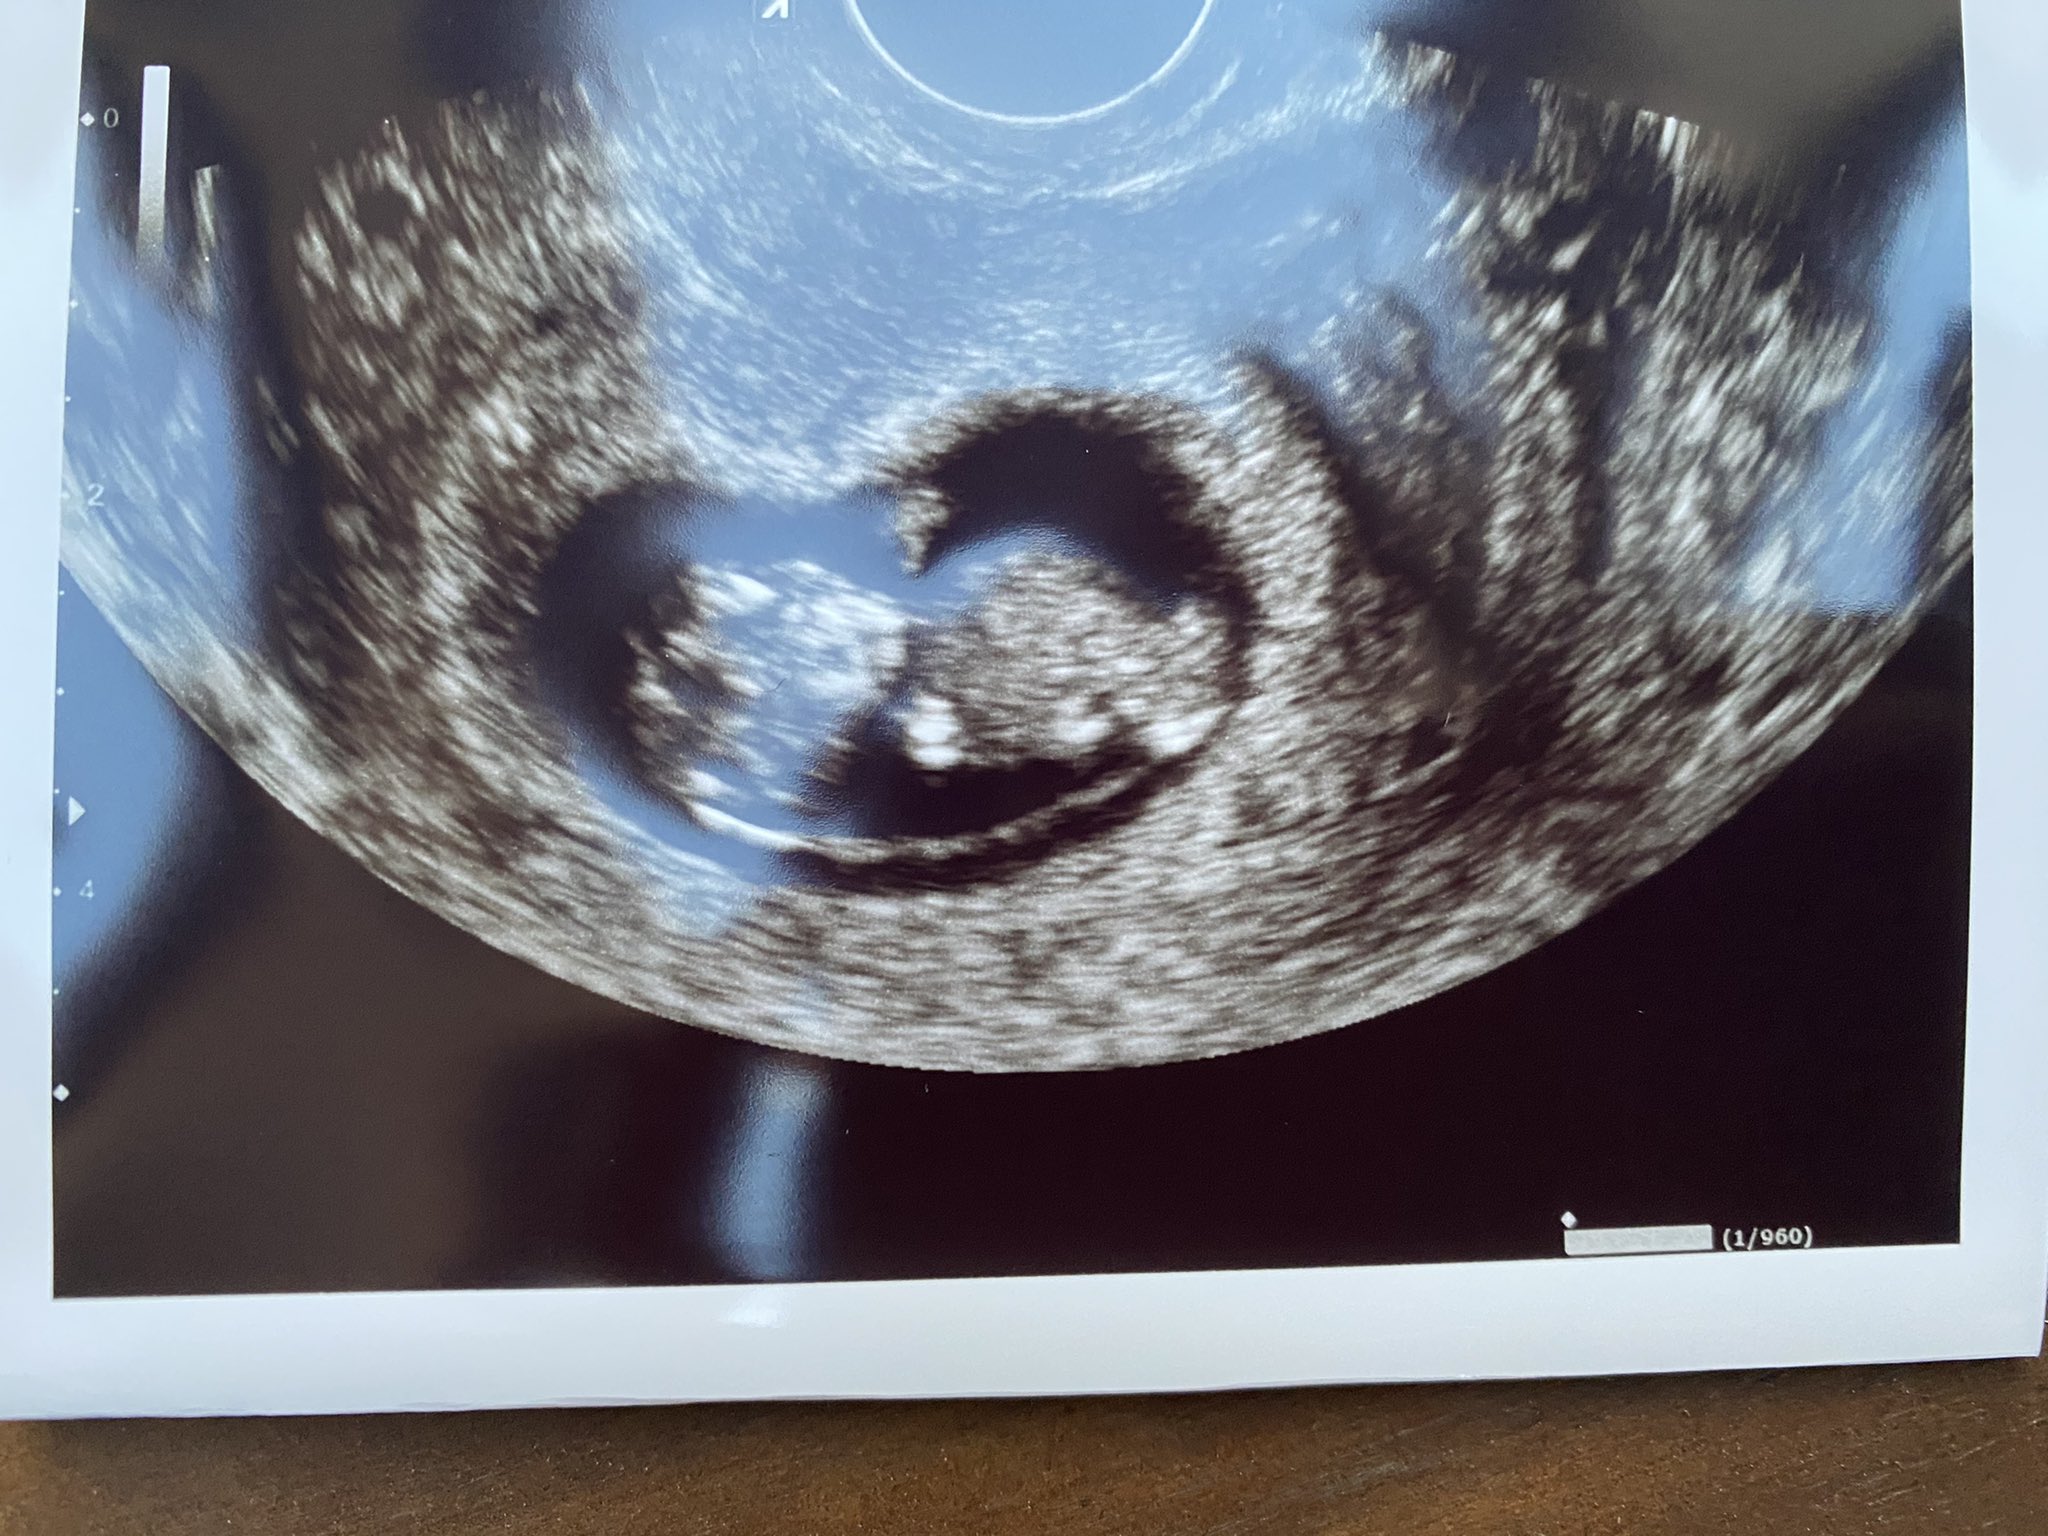

baby at 10 weeks 4 days ultrasound

Mar 23 2021 at 712 PM I am 10 weeks 4 days today and I had my first ultrasound it was extremely exciting and beautiful. All the bones are growing and maturing at. I am 10 weeks 4 days today and I had my first ultrasound it was extremely exciting and beautiful.

. Caught on camera some of the first movement of our future child at only 10 weeks in the womb. Your Babys Development at 10 Weeks At week 10 a baby is about 1 14 to 1 12 inches long 354 centimeters. The rest cells of a gestational sac will play a role in the development of muscles eyelashes and skin which will take some time though.

The black bubble is the amniotic sac of the fetus. Those sacs will merge later and they will likely each have their own. The first ultrasound done between 10 and 14 weeks is considered the most accurate method of estimating when you conceived.